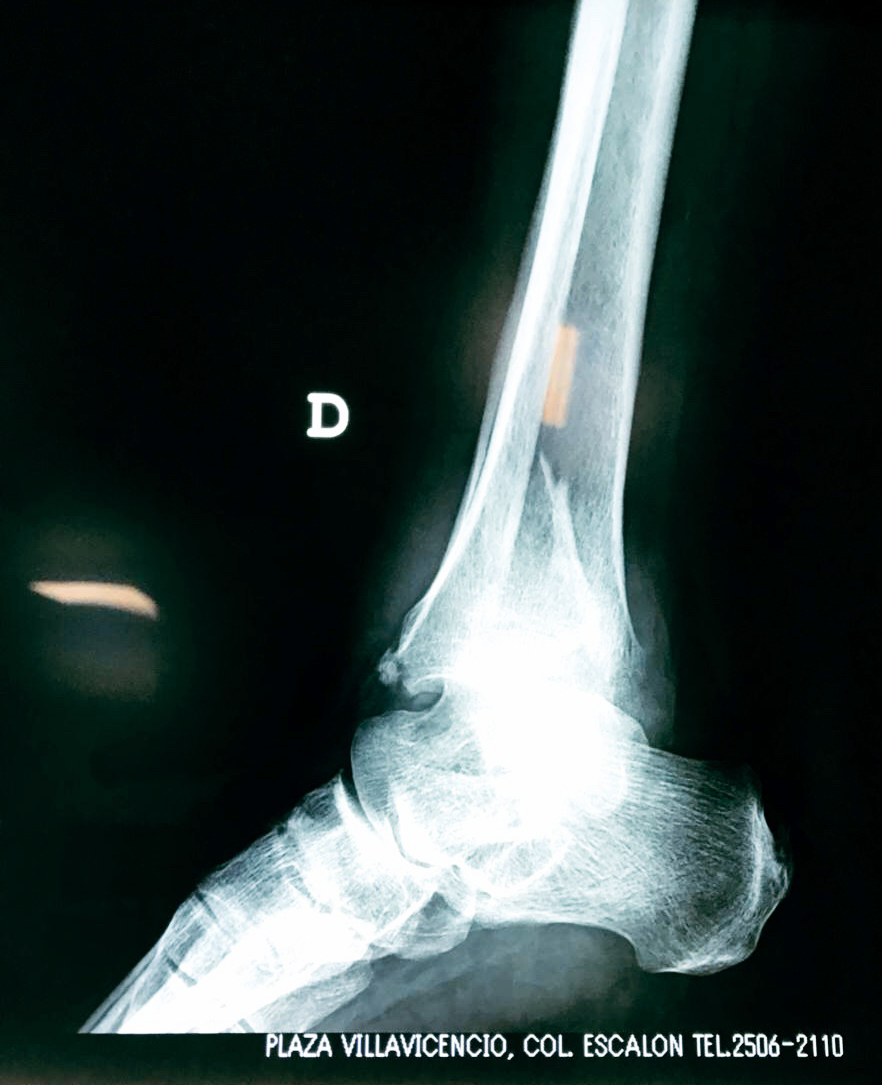

Una fractura de tobillo es la rotura de uno o más de los huesos del tobillo. Estas fracturas pueden ser:

Algunas fracturas de tobillo pueden requerir cirugía si:

- Los extremos de los huesos están desalineados entre sí (desplazados).

- La fractura se extiende hasta la articulación del tobillo (fractura intra-articular).

- Los tendones o ligamentos (tejidos que sujetan los músculos y los huesos entre sí) están rotos.

Cuando se necesita cirugía, es probable que esta implique el uso de clavijas de metal, tornillos o placas para sostener los huesos en su lugar mientras la fractura se consolida. Los elementos de soporte pueden ser temporales o permanentes.